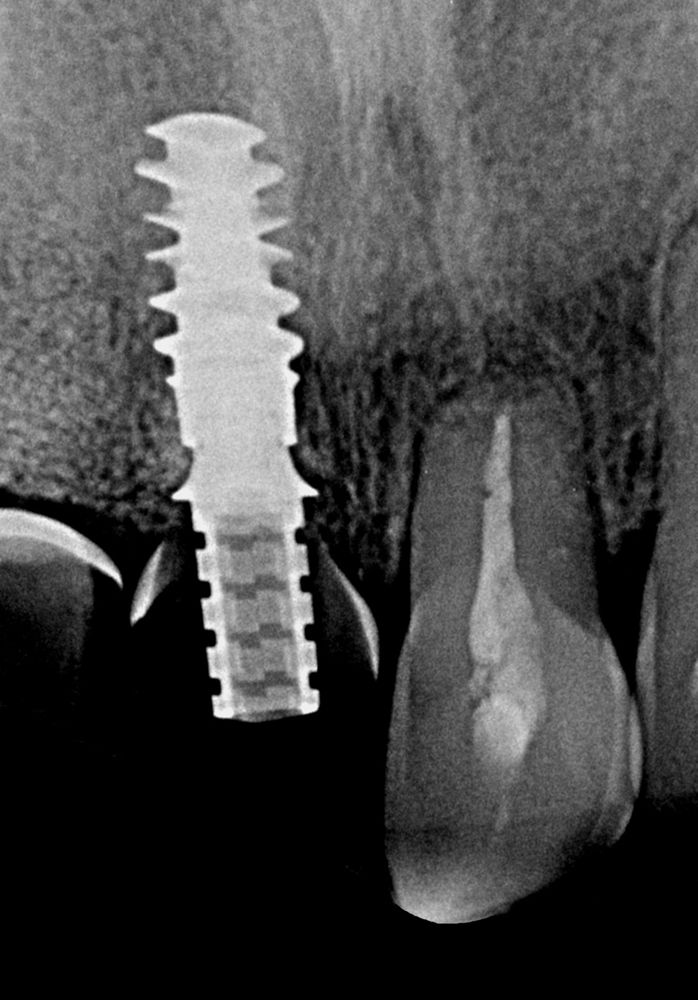

Re-directing of drilling and implant placement ensures avoiding socket apex and entering the palatal plate. This leaves a gap between implant and buccal plate which can be filled with slow resorption bone graft. Straumann® VeloDrill™ System, and patient’s denture was used as a surgical guide. (Figs. 5-6) Parallelism pin, and radiographic control. (Figs. 7-8)

A Straumann® BLX 4.5 ø x 10 mm implant was placed, slightly palatal inclination, into the upper right central incisor’s socket, with an optimal insertion torque. Implant per se doesn’t secure optimal esthetic results. It is mandatory to use biomaterials if we mean to maintain bone contour and gain gingival width and thickness.